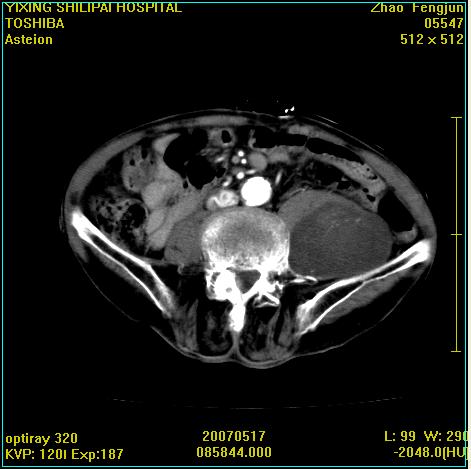

考虑:1、左侧腰大肌囊实性占位性病变(囊性神经根鞘瘤?);

2、右侧兰尾区囊性占位性病变(兰尾囊肿?囊腺癌?类癌?)

以下是引用xiaoniu在2007-5-26 10:45:00的发言:[br]腰大肌的病变应该没有问题,增强扫描还有轻度强化及细小血管影入内,应该排除脓肿,考虑占位性病变,腰大肌的占位多考虑:神经源性肿瘤。另外腹主动脉下端有真假腔的强化,考虑:主动脉夹层。[br][br][本贴已被 xiaoniu 于 2007-5-26 10:46:39 修改过]

以下是引用老爱克斯新网客在2007-5-26 18:26:00的发言:[br]1左下腹囊实性占位肿块,增强后不均匀强化,位于脊柱旁,椎体骨质无破坏软组织无肿胀,考虑神经源肿瘤神经鞘瘤可能大,2右下腹囊性占位性病变,增强后囊壁强化,考虑阑尾囊肿或囊腺瘤,